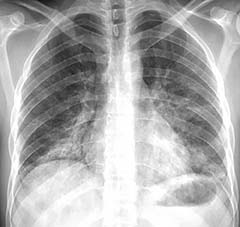

In one case highlighted in the report, Drs. Abbara and Kay illustrate some of the radiographic and CT findings of lung injury in the clinical case of a 24-year-old male patient with past medical history of asthma, who presented with shortness of breath, productive cough, chest pain and fever for one week. The patient reported current daily use of e-cigarettes (with tobacco) and marijuana, without substantial change in recent vaping habits. He had high white cell and platelet counts.

The radiologic findings included bilateral basilar predominant ground-glass and reticular opacities in both lungs. Histologic specimens obtained from the right lower lobe at biopsy were suggestive of lipoid pneumonia, according to the report. The patient was given steroids with a presumptive diagnosis of lung injury associated with e-cigarette use.

“The diagnosis of lung injury due to e-cigarette use should be a differential possibility in patients presenting with bilateral lung opacities on radiographs or ground-glass opacities on chest CT images and exposure to e-cigarette products within 90 days of the presentation,” Dr. Abbara said.